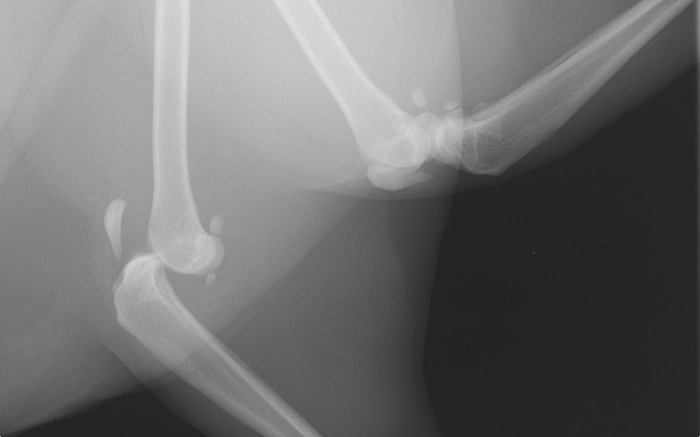

| Pruebas | La radiografía expone una amplia luxación femoro-tibial sin fracturas aunque con una gran inflamación de rodilla. La cápsula parece íntegra. El ligamento cruzado caudal está roto pero el craneal no es valorable. Obviamente en este caso hay grandes limitaciones para la exploración incluso bajo anestesia. |

La radiografía tomada de urgencias con el animal despierto apunta hacia una lesión grave aunque poco clara sobre todo por lo infrecuente de la lesión.

La posición laterolateral nos da el detalle de lo que está pasando. A pesar de esto hay cierta movilidad de flexión de unos 30º.